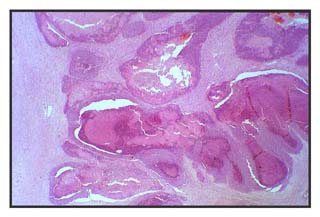

Figura 1: Tumoración de 10 x 3,5 cms de consistencia firme y coloración blanquecina.

Localizada en dermis y tejido subcutáneo, extendiéndose a partes blandas adyacentes (tejido periarticular), que ulcera y deprime la piel.